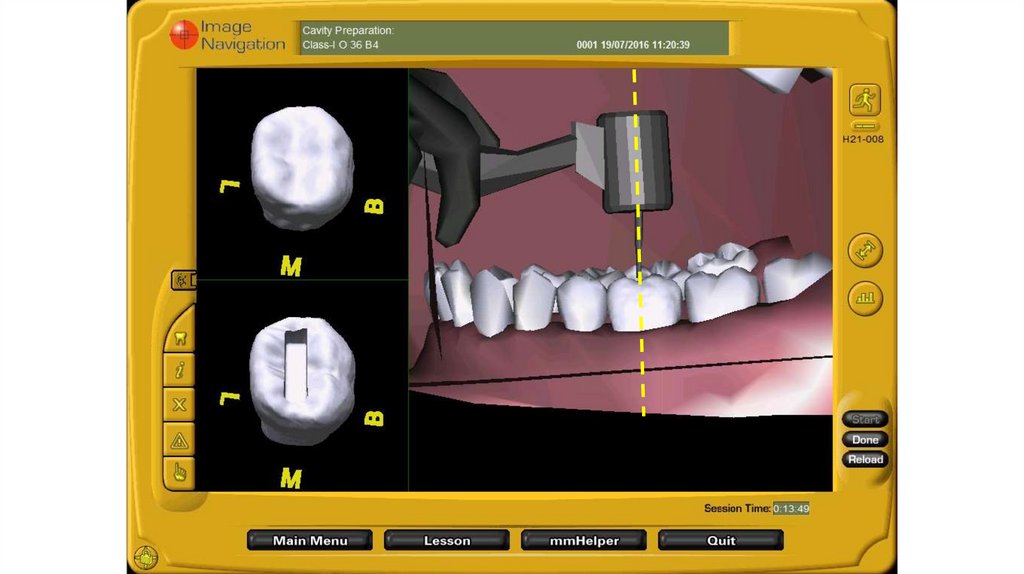

ИНТЕРФЕЙС DENTSIM

18. ИНТЕРФЕЙС DENTSIM

1

2

19. ИНТЕРФЕЙС DENTSIM

20. ИНТЕРФЕЙС DENTSIM